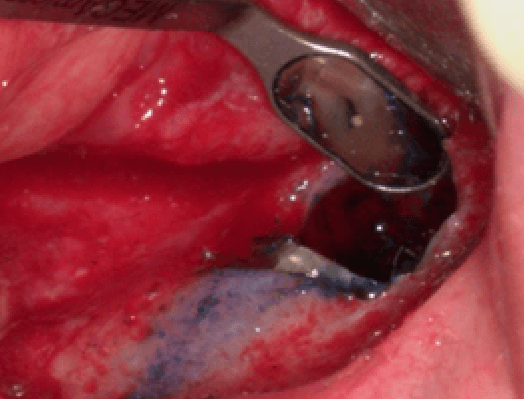

患者原本就有一組牙橋,但其中一顆牙長了膿包,X光檢查發線有根尖周圍炎的狀況,若要拆除重新根管治療療程會較長且需要再多負擔新假牙之費用,用手術可以快速的處理此類病例

切除感染最嚴重的牙根部分

顯微鏡底下檢查牙根是否有斷裂之情況

以生物水泥置換原本的封填材料,以達到更好的治療品質